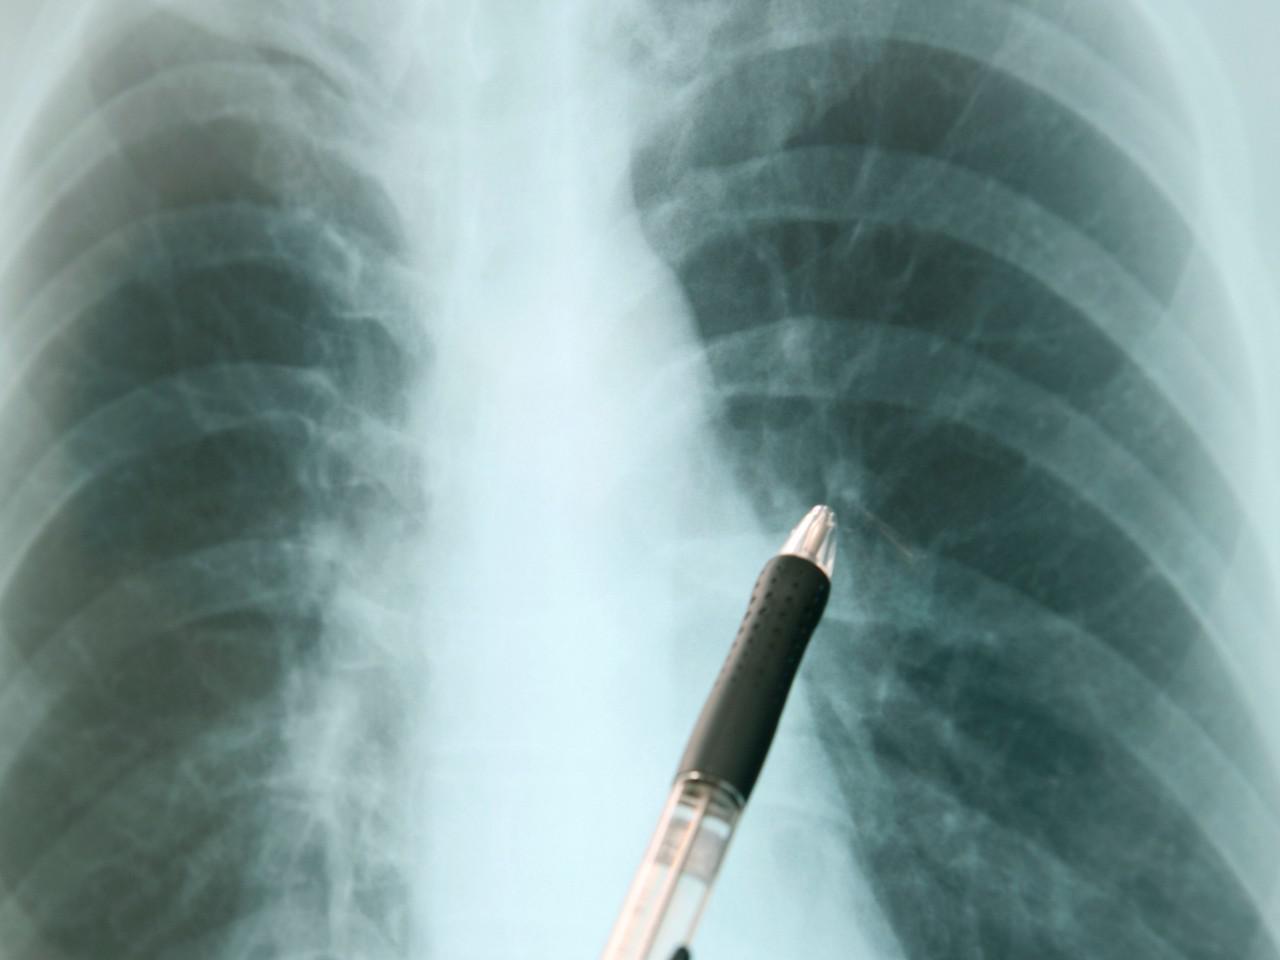

Tubercolosi: minaccia numero uno per casi e decessi – report Oms

La tubercolosi (Tbc) torna in primo piano come principale malattia infettiva mortale, con una diffusione globale e un bilancio che ha superato i livelli del 2022, raggiungendo 8,2 milioni di nuovi casi diagnosticati nel 2023. Secondo l’ultimo Global Tuberculosis Report dell’Organizzazione Mondiale della Sanità (Oms), questo è il più alto tasso registrato dal 1995, quando l'Oms iniziò il monitoraggio globale. I casi di Tbc registrati nel 2023 rappresentano un aumento significativo rispetto ai 7,5 milioni dell’anno precedente, mentre si stima che 10,8 milioni di persone abbiano contratto la malattia.

Nel 2023, la Tbc ha causato circa 1,25 milioni di decessi, confermandosi una minaccia importante, soprattutto in 30 Paesi con alti tassi di incidenza, tra cui India, Indonesia, Cina, Filippine e Pakistan, che insieme contano l’87% dei casi mondiali. L’India è il Paese più colpito, con circa il 26% delle infezioni globali. Un altro dato preoccupante riguarda l'aumento della Tbc multiresistente (Mdr-Tbc), un ceppo resistente ai trattamenti convenzionali: circa 400.000 persone hanno sviluppato questa forma della malattia, ma solo il 44% ha ricevuto una diagnosi e un trattamento adeguato.